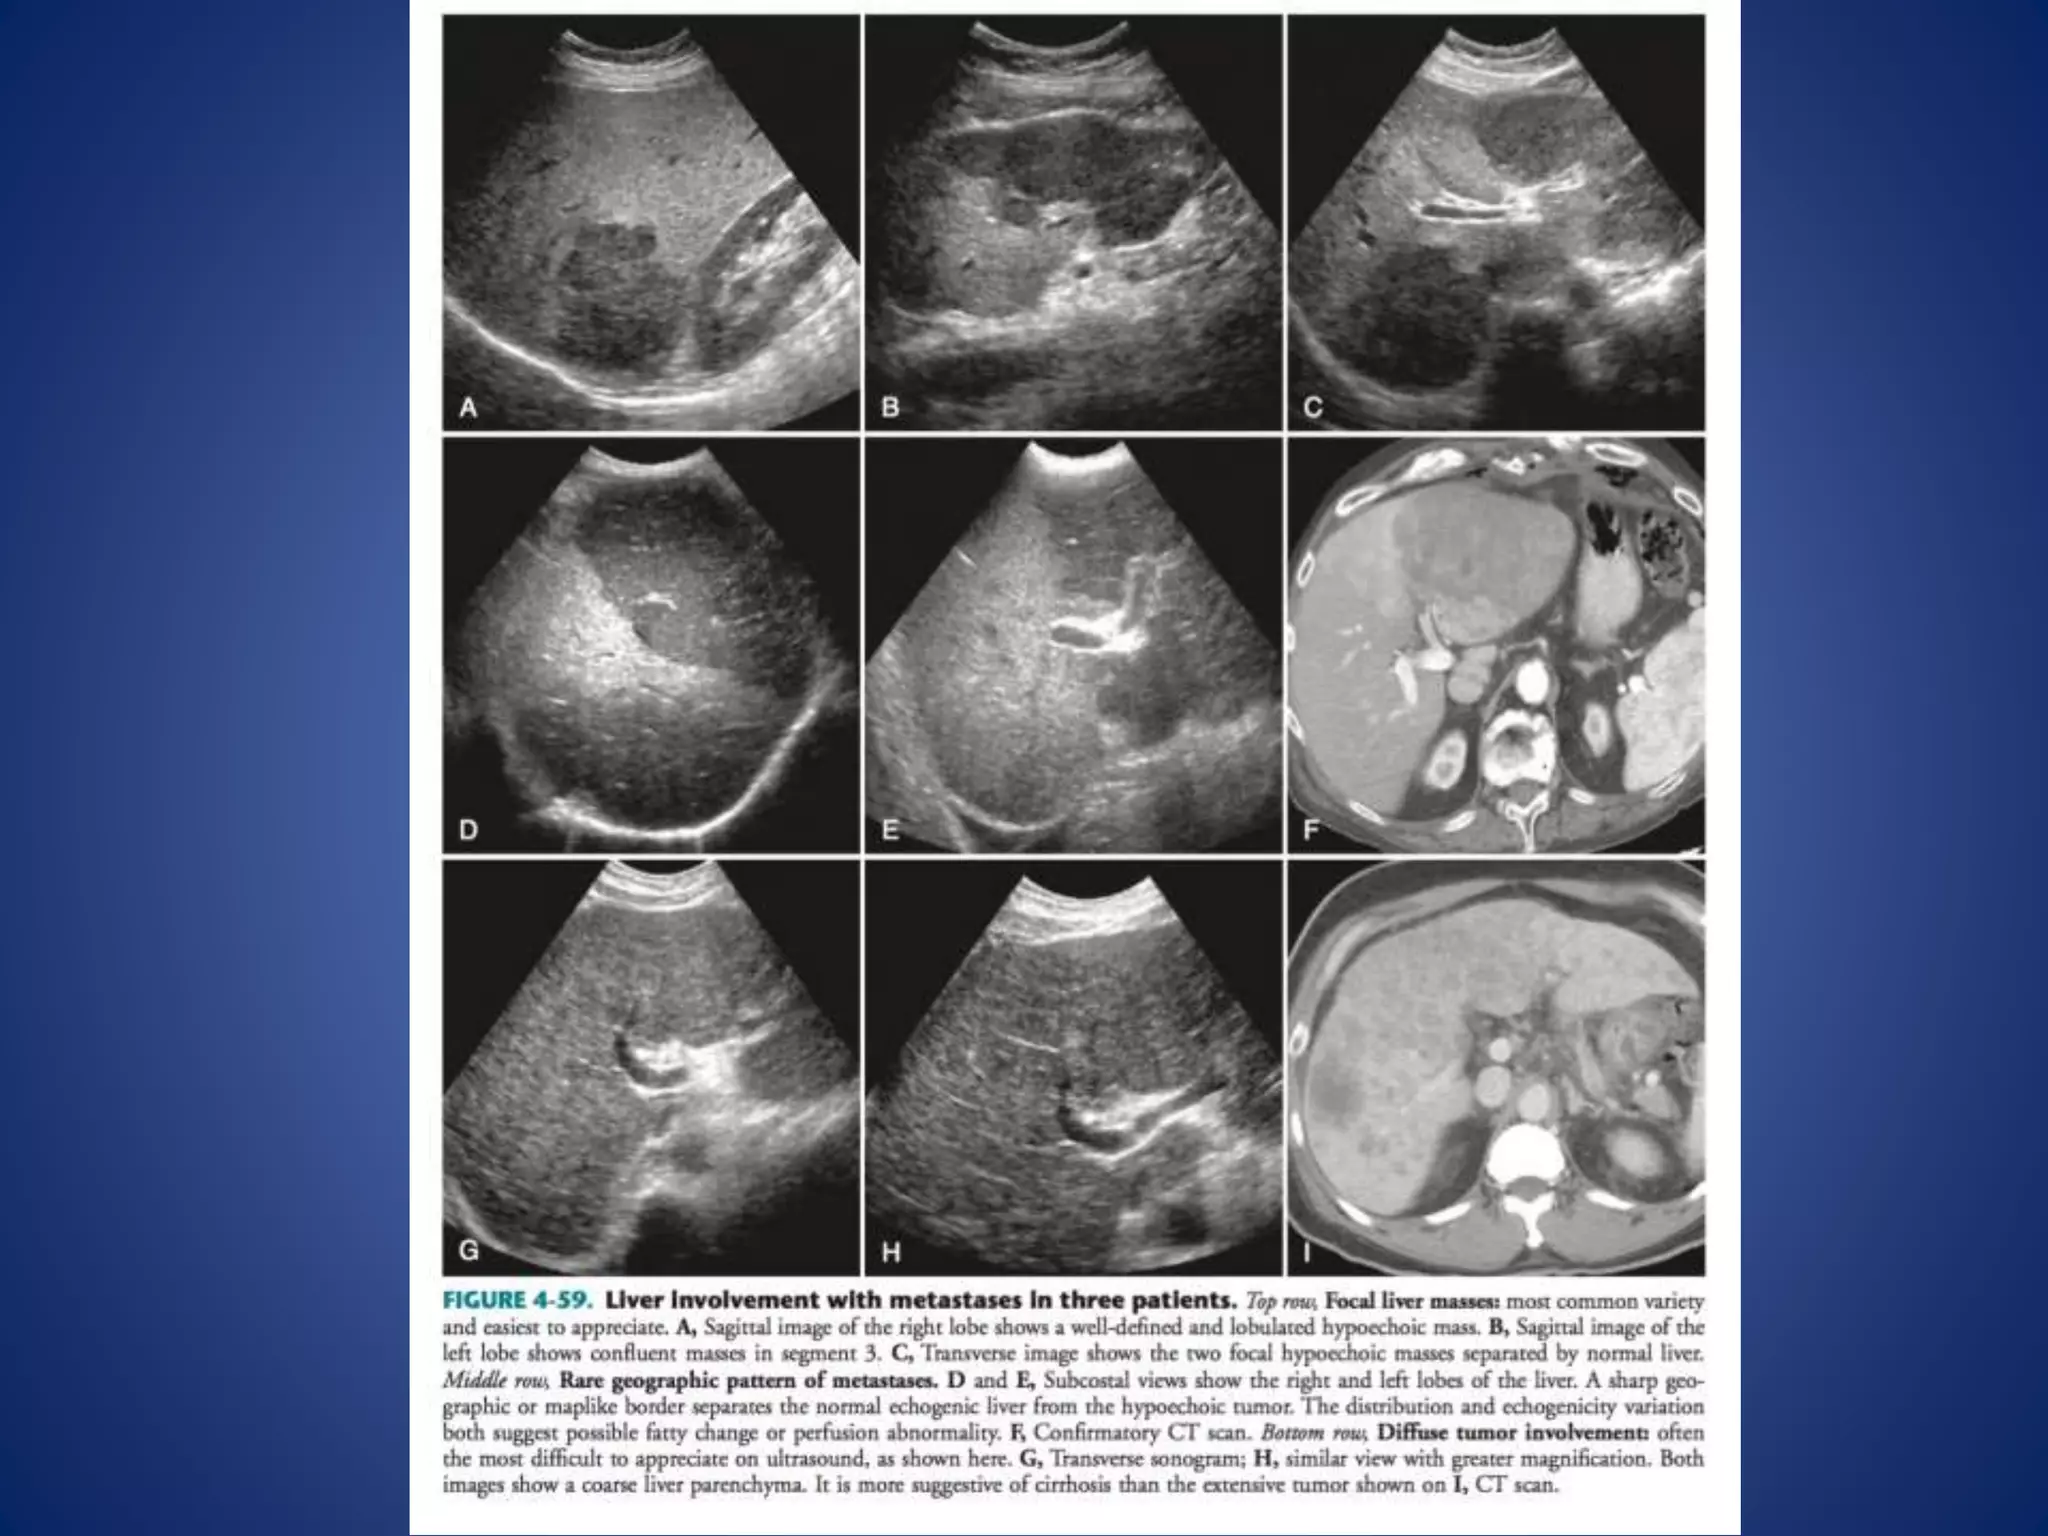

This document discusses various malignant liver lesions including hepatocellular carcinoma (HCC), liver metastases, and angiosarcoma. HCC is the most common primary liver cancer, often occurring in cirrhotic livers, and can appear solitary or multifocal on imaging. Liver metastases commonly spread from gastrointestinal or non-gastrointestinal primary cancers via the hepatic artery or portal vein. Angiosarcoma is a rare malignant vascular liver tumor associated with toxins like polyvinylchloride and arsenic.